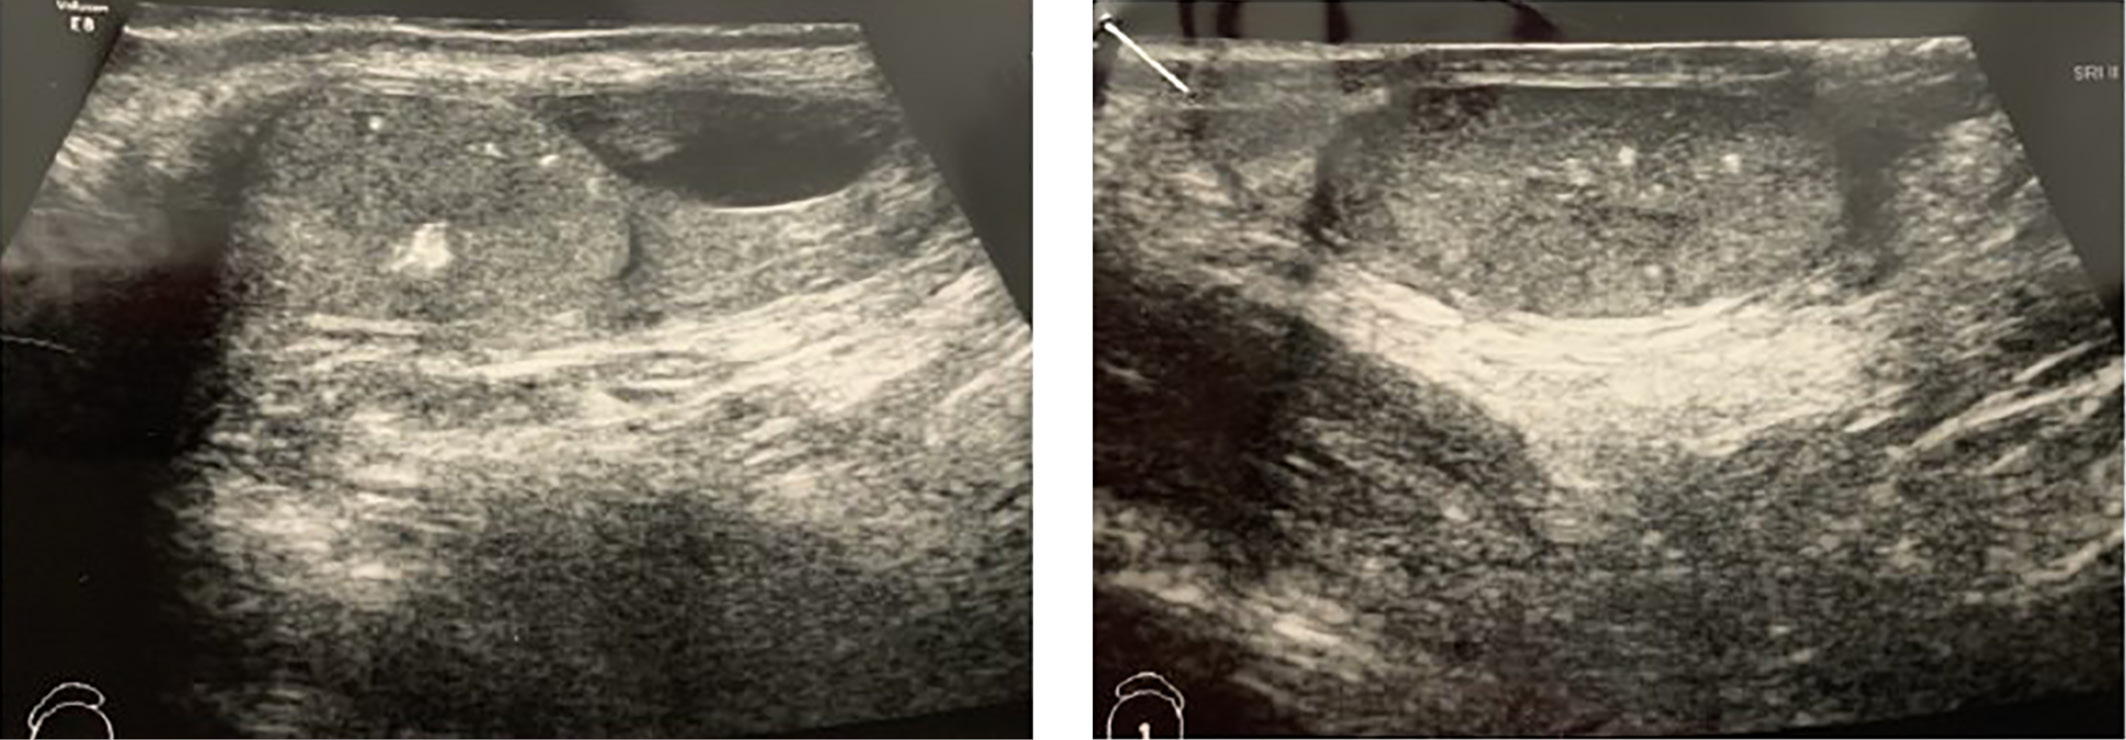

1. Figure 1. Ultrasound of the scrotum of patient S. at the age of 4.7 years. | |

2. Figure 2. Ultrasound of the scrotum of patient S. at the age of 6 years. | |